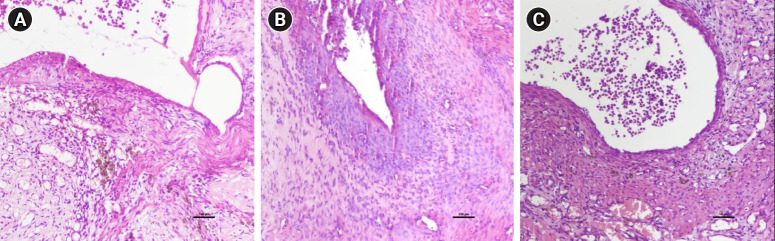

Methods: In this study, our objective was to assess the therapeutic mechanisms of the onion bulb A. cepa using an autologous endometriosis model in Sprague-Dawley rats. Previous research has shown that A. cepa possesses anti-inflammatory, antioxidant, and antiapoptotic properties. We evaluated the pathological condition of endometriotic implants by employing hematoxylin-eosin staining and Ki67 immunohistochemistry analysis. Transforming growth factor-beta 1 (TGF-β1) and alpha-smooth muscle actin (α-SMA) have been identified as profibrotic markers that are highly overexpressed in endometriotic tissues relative to eutopic endometrial tissue. Furthermore, TGF-β1 influences the differentiation and progression of endometriosis. To quantify profibrotic activity, we measured TGF-β1 and α-SMA using the immunosorbent assay method.

Results: Lower histologic evaluation scores for endometriotic implants were observed in the group receiving high-dose A. cepa relative to the other groups. Ki67 expression was reduced following the high-dose A. cepa regimen, which consisted of 30% A. cepa and 70% normal feed. However, no statistically significant differences in TGF-β1 or α-SMA levels were observed among the groups (p=0.7 and p=0.778, respectively).